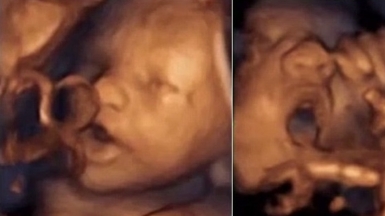

But when music was emitted via the Babypod, 87 percent of foetuses reacted with head and limb movements. Moreover, they moved their mouth and tongue, which stopped when the music stopped.

The researchers also found out that 50 percent of the foetuses opened their jaw very wide and sticked out their tongue out as far as it would go when they started hearing the music.